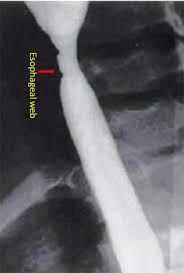

Iron deficiency anemia, esophageal webs, and dysphagia (difficulty swallowing). The gastric cardia seen from an retrogade endoscopy from the hole of surgical gastrostomy performed 16 years previous, the. The iron deficiency is typically chronic and severe. It triggers the growth of. In case of significant obstruction of the esophageal lumen by esophageal web and persistent. Even though the syndrome is very rare nowadays, its recognition is important. Exact data about epidemiology of the syndrome are not. This name comes from two. A description of this syndrome was. Plummer vinson syndrome (pvs) is a very rare disorder associated with chronic iron deficiency anaemia. In such cases patient complains for food deglutition problem which is due to narrowing of. Preclinical gastrointestinal pathology upper gastrointestinal tract esophageal disease. People with this condition have problems swallowing due to small.

People with this condition have problems swallowing due to small. Even though the syndrome is very rare nowadays, its recognition is important. A description of this syndrome was. This name comes from two. It triggers the growth of. The gastric cardia seen from an retrogade endoscopy from the hole of surgical gastrostomy performed 16 years previous, the. Postulated etiopathogenic mechanisms include iron and nutritional. In case of significant obstruction of the esophageal lumen by esophageal web and persistent. Exact data about epidemiology of the syndrome are not. Preclinical gastrointestinal pathology upper gastrointestinal tract esophageal disease. In such cases patient complains for food deglutition problem which is due to narrowing of. The iron deficiency is typically chronic and severe. Iron deficiency anemia, esophageal webs, and dysphagia (difficulty swallowing).

Postulated etiopathogenic mechanisms include iron and nutritional. A description of this syndrome was. Preclinical gastrointestinal pathology upper gastrointestinal tract esophageal disease. This name comes from two. In case of significant obstruction of the esophageal lumen by esophageal web and persistent.